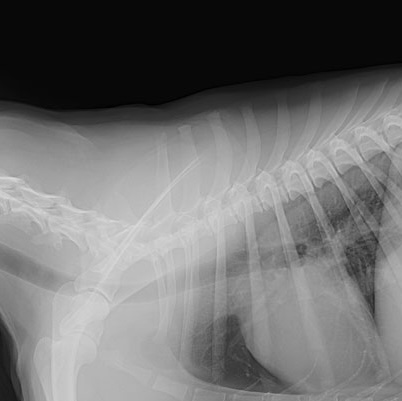

Digital Radiography

Here at Fountain City Animal Hospital, we offer the latest in diagnostic imaging equipment. Radiographs and ultrasound imaging can be important in diagnosing many life-threatening problems. Our veterinary hospital has the in house capabilities of performing radiographs on your pet. Radiographs can be used to diagnose fractured bones, intestinal foreign bodies, bladder stones, and can be a useful tool in cardiac disease. Ultrasound imaging can be used for looking at internal organs such as the liver and kidneys, assessing an animal for pregnancy, or diagnosing abdominal tumors. We have a brand new, state of the art Ultrasound machine in order to provide your pet with the most up to date care.